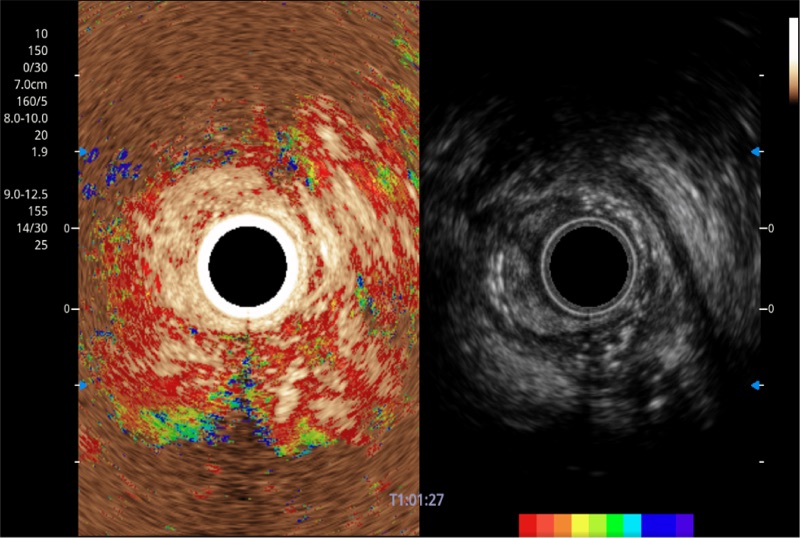

肝左叶和肝静脉的横截面

可人为将灰阶图像转变成彩色的显示方式,增强人眼对于不同回声强度的敏感度,主观上增加了图像分辨率

微米成像技术提升了对组织斑点噪声信号的抑制能力,并进一步强化边界信息,从而获得信噪比更优、边界更清楚锐利的图像

随着组织深度的变化,超声接收频率进行智能匹配跟踪,确保图像中、远场良好的穿透力以及整场一致的分辨力,从而得到均一的画质